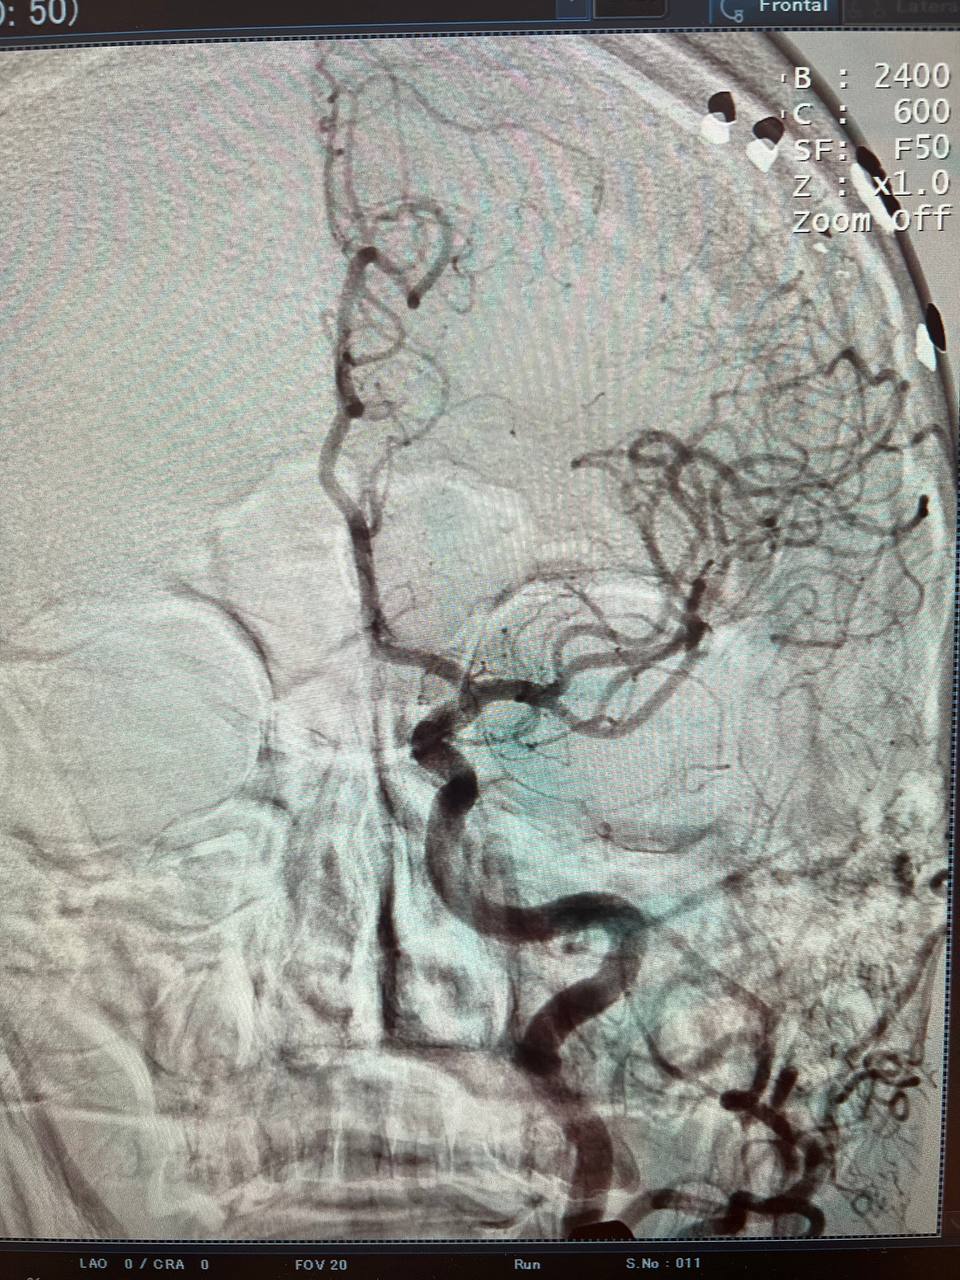

На ангіографічній системі Infinix 2011 року випуску вперше в історії госпіталя провели ургентне стентування та балонну ангіопластику лівої внутрішньої сонної артерії.

У відділення неврології поступив пацієнт з повторним ішемічним атеротромботичним інсультом в басейні лівої СМА  з елементами моторної афазії. Атеросклеротична субоклюзія (85%) С1 сегменту лівої внутрішньої сонної артерії. Дисліпідемія. Гіпертонічна хвороба ІІІ ст., 3 ст., ризик 4.

Терміново проведено ургентне оперативне втручання: ендоваскулярне стентування стенотичного ураження гирла С1 сегменту лівої внутрішньої сонної артерії. Селективна церебральна ангіографія. Це була дуже складна операція, але пройшла успішно. Відкрили ЛВСА на 90%.

Результати дослідження до та після ургентного оперативного втручання: